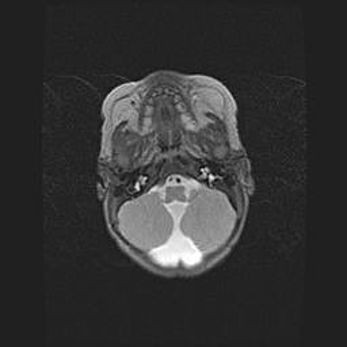

Подострая гематома правой гемисферы мозжечка.

Наружная гидроцефалия.

Возраст: 15 дней

Вес: 3100 г

Пол: женский

Окружность головы: 37 см

Срок гестации: 35-36 недель

При открытой наружной форме гидроцефалии у новорожденных расширяются и переполняются субарахноидные пространства.

Кровоизлияния в мозжечок имеют две клинико-анатомические формы: полушарные гематомы и кровоизлияния в червь.

К появлению этой патологии может привести: повреждения головного мозга, возникающие в результате асфиксии и гипоксии плода при беременности, или травмы во время родов. Редко гематома мозжечка может быть результатом первичной коагулопатии и сосудистой мальформации, диссеминированном внутрисосудистом свертывании, изоиммунной тромбоцитопении.